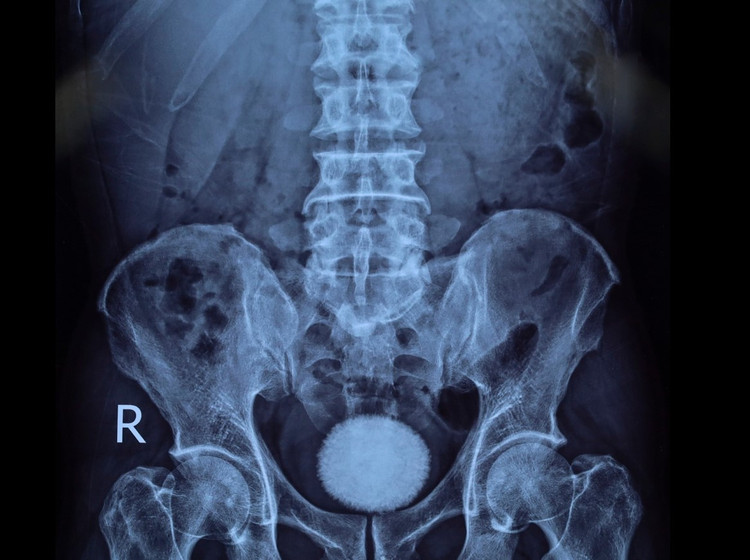

Trên siêu âm và chụp X-quang đều cho hình ảnh sỏi bàng quang kích thước lớn 60x40 mm. Vì vậy, các bác sĩ đã chỉ định người bệnh phẫu thuật lấy sỏi bàng quang.

Viên sỏi bàng quang trên phim chụp - Ảnh BVCC

Trong quá trình phẫu thuật, ê-kíp tiến hành rạch da đường giữa trên xương mu, tiếp cận bàng quang và lấy ra một viên sỏi lớn có kích thước và hình dáng như trên phim, lớn như một quả trứng ngỗng. Sau đó bàng quang được bơm rửa sạch và khâu phục hồi theo đúng quy trình chuyên môn.